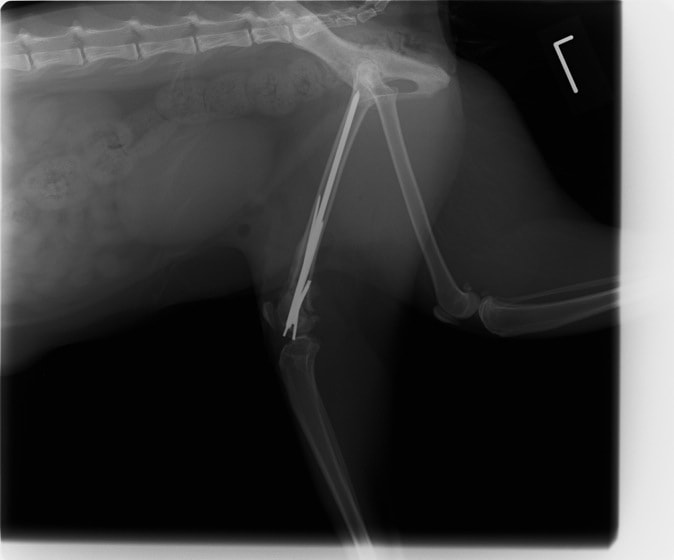

症例3:キルシュナーワイヤーのピンニングによる整復

ペルシャ猫 11ヶ月齢 雄

他院にて左大腿骨遠位の成長板骨折(salter-harrisⅠ型)が認められており、治療相談を目的として来院。当院にて、キルシュナーワイヤーを用いたピンニングにより骨折部位の整復を行いました。術後の経過は良好で、現在も経過観察中です。

術前レントゲン

術後レントゲン

Arthrex社のターゲティングデバイスを用いてピンニングの位置を調整することで、確実な固定を行っています。当院ではこの手術器具以外にも、人の手術にも使用される様々な器具を導入し、手術精度を高め、また医療メーカーと新しい器具の開発、試作にも取り組んでおります。